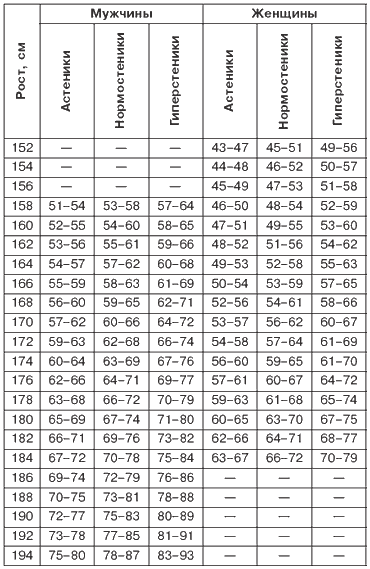

Медицина выделяет три типа телосложения: астенический, нормостенический и гиперстенический. Главным признаком, определяющим принадлежность фигуры к тому или иному типу, является длина туловища, которая вычисляется по следующей формуле: расстояние от лонного сочленения до выреза грудины, поделенное на рост и умноженное на 100. Этот показатель с учетом особенностей человеческого тела очень широко используется в традиционной медицине.

У астеников узкое длинное тело с плоской узкой и длинной грудной клеткой, длинная шея, длинные тонкие руки и ноги, узкое продолговатое лицо. Мускулатура развита слабо. У нормостеников мускулатура при среднем телосложении хорошо развита, а гиперстеники ширококостные, коренастые и, как правило, склонны к полноте.

В табл. 1 приведены средние показатели массы тела в зависимости от роста женщины. Таблица составлена применимо к возрасту 25–30 лет; каждое следующее десятилетие дает вам право на прибавку в 1 к г.

Таблица 1

Нормальное соотношение массы тела и роста и типа сложения, кг